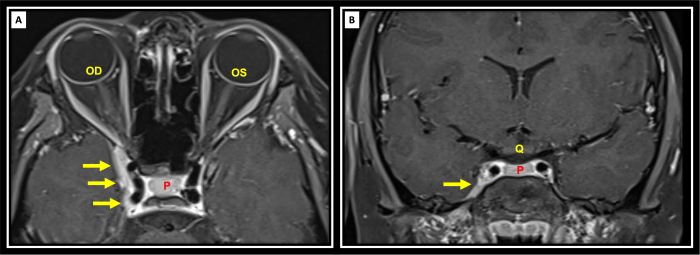

Diagnosis is clinical and radiologic, based on characteristic findings and exclusion of other causes of painful ophthalmoplegia. The most appropriate imaging includes MRI /MRA (DWI series) which provides information about the cavernous sinus and orbital apex in greater detail than a CT. MRI may be able to provide detail of granulomatous inflammation, aiding in formal diagnosis of Tolosa-Hunt syndrome. However, these results may be unreliable. Biopsy can also be used to demonstrate granulomatous inflammation and may be more reliable, but the procedure may be more difficult[9]

Recent evidence supports the use of High resolution 3D skull base MRI with isotropic constructive interference in steady state (CISS) and 0.6-mm cut images with and without contrast as effective way to visualize cranial nerves and cavernous sinus lesions that were not previously visualized.[11]

A. Imaging

- MRI with contrast is the gold standard.

- Typical findings:

- Enlargement and contrast enhancement of the cavernous sinus or superior orbital fissure.

- Possible extension into the orbital apex.

- Iso- or hypointense T1 signal; variable T2 signal.

CT may show nonspecific soft tissue density.